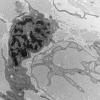

PERIPHERAL NEUROPATHY

4 AXONAL DEGENERATION

3 Electron Microscopy (6)